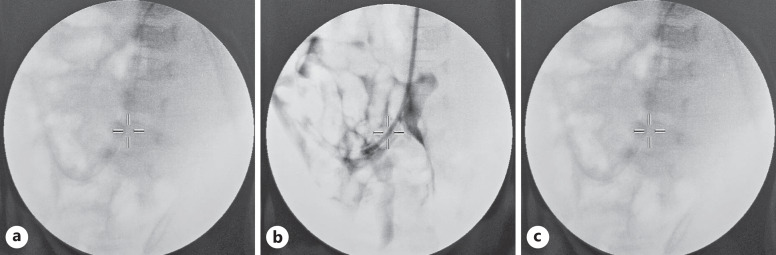

Case presentation: We reported a case of PD catheter adhesion to the ileum in a 1-year-old girl. Previously, the patient underwent laparoscopic insertion of PD catheter due to ESKD. One month after the procedure, there were signs of catheter obstruction. Laparoscopy evaluation and revision were carried out.